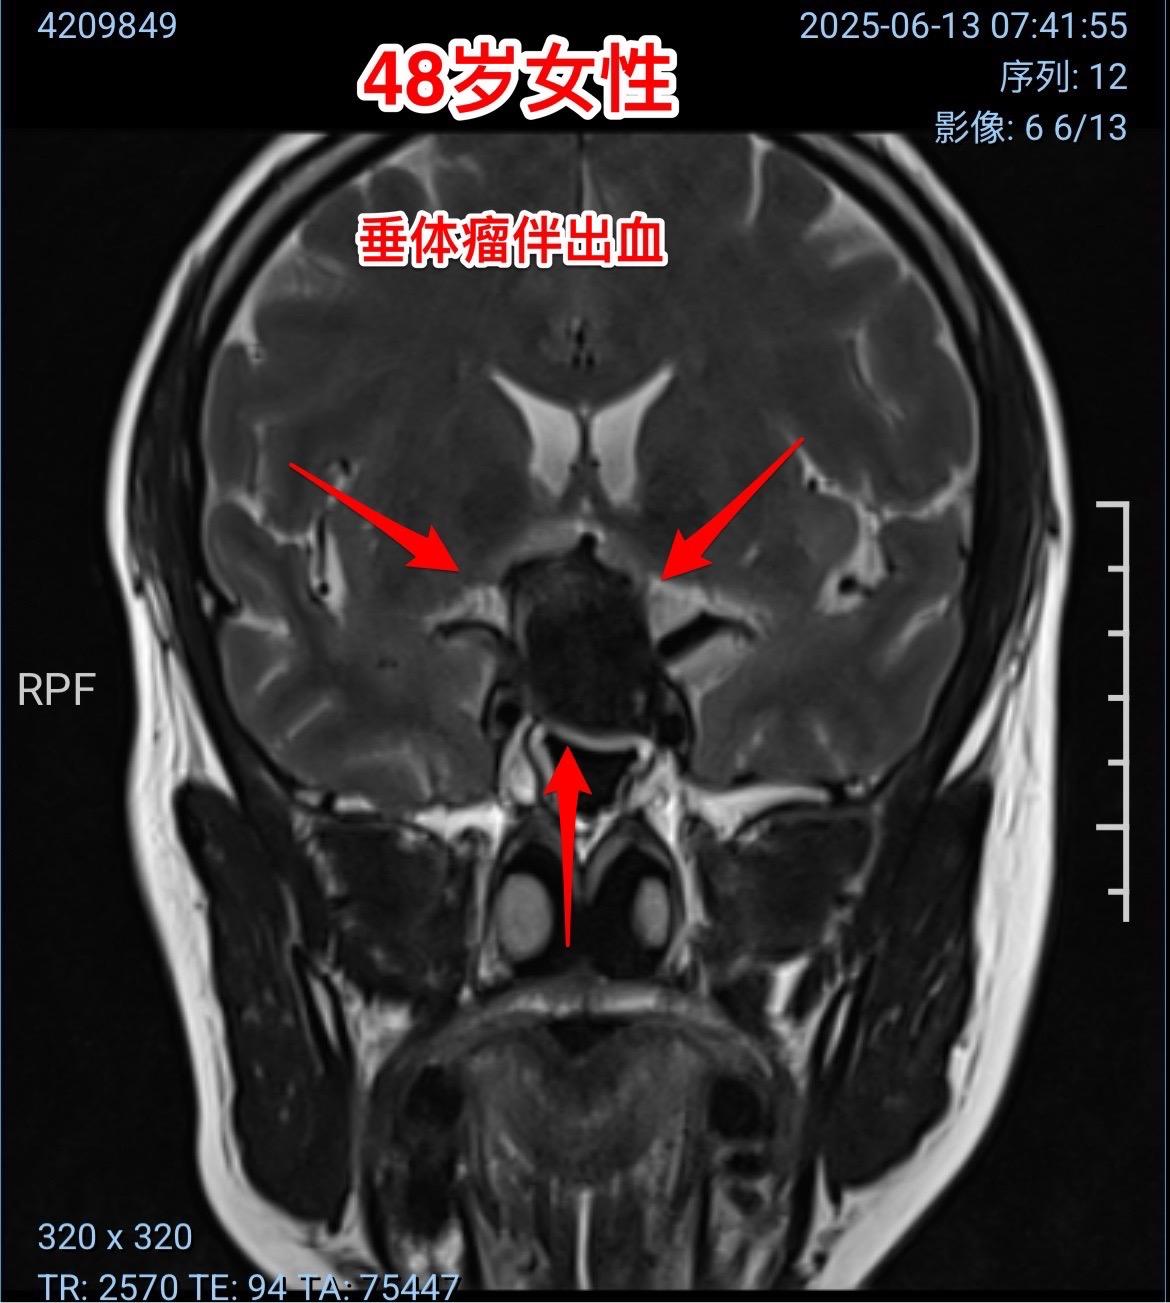

垂体瘤卒中,女教师6月12日突发视力下降。48岁定州市女教师6月12日早晨起床时尚无不适,上午出现眼前发花、白一块黑一块,随后双眼视力下降,几乎失明。 到当地医院行头部CT检查发现鞍区出血了,怀疑是动脉瘤破裂,随后作了磁共振、MRA检查,排除了动脉瘤破裂,诊断为垂体瘤卒中。 6月13日上午患者一家人自驾车出发,中午到了三博脑科医院。下午急诊行经鼻手术切除垂体瘤。 时间紧迫,极力挽救视力。 6月14日早晨患者自述视力有好转。